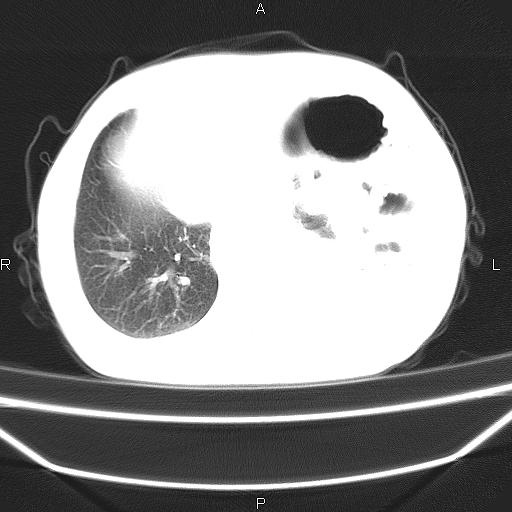

患者,男。50岁。近几日有咳嗽症状,无其他不适,既往病史无,考虑膈疝。请前辈们看看指导指导。

膈膨升,左下肺通气不良,膈肌好像还完整。

考虑左侧膈疝。

左侧膈疝。

符合隔膨升,膈肌较完整。